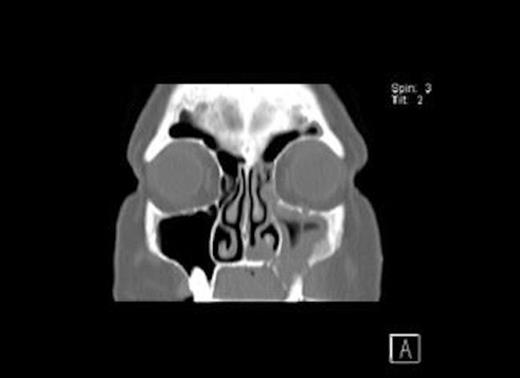

CT Scans (Fig. 1& 2) showed opacity and thickening of the left maxillary antrum with dehiscence of the medio-inferior and anterior walls of the sinus and a maxillo-oral fistula. There was destruction of bone in the floor of the left maxillary sinus consistent with an area of osteonecrosis secondary to bisphosphonate.

Coronal CT Scan of the head showing osseo-sclerotic changes / oroantral fistula floor of left maxillary sinus